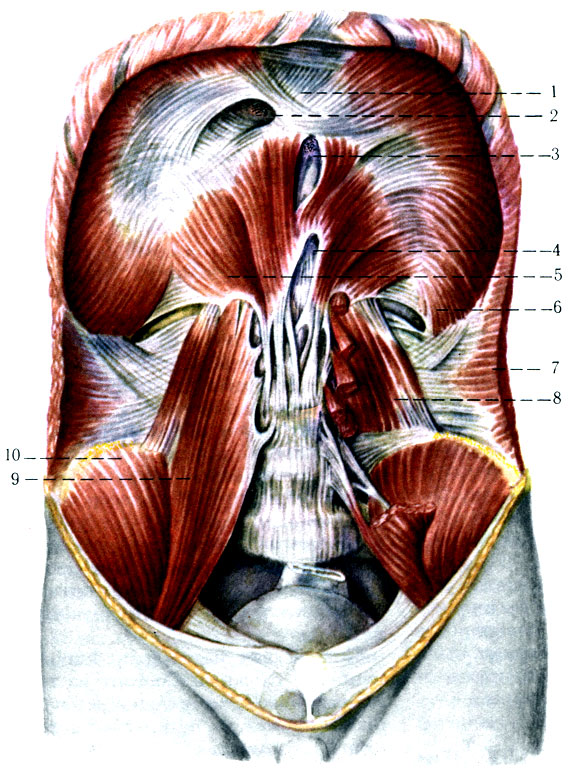

Анатомия диафрагмы и треугольника Бохдалека

Раздел: Визуальный дайджест